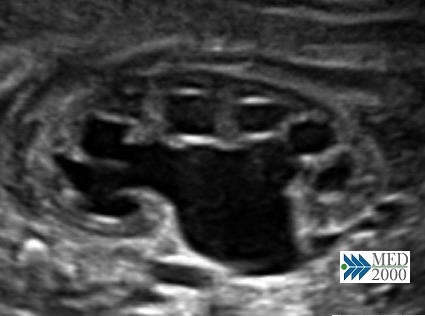

• pielectasia e calicectasia: consiste nella dilatazione della pelvi o bacinetto e dei calici; la diagnosi di pielectasia è effettuata allorquando il diametro antero-posteriore della pelvi è superiore ai 7 mm. Nelle forme severe di pielo-calicectasia si ha compressione del parenchima renale con successiva corticalizzazione.